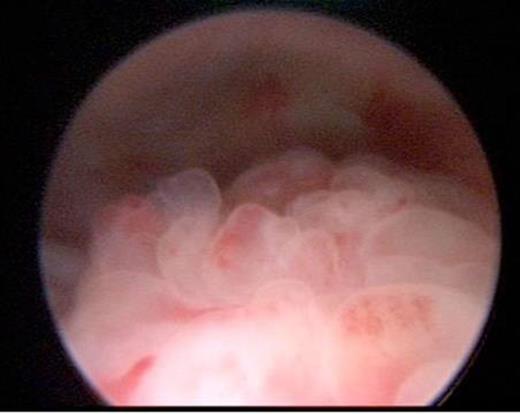

The diverticulum was clearly seen on micturating cystourethrogram (MCUG). Subsequent magnetic resonance imaging (MRI) scan confirmed the presence of a large bladder diverticulum and also demonstrated an enhancing, irregular, nodular posterior bladder wall thickening which was confined to the bladder. Cystoscopy revealed a papillary lesion on the posterior bladder wall adjacent to the diverticulum opening (figure 2).

Ultrasound images demonstrating a posterior bladder wall lesion with increased vascularity